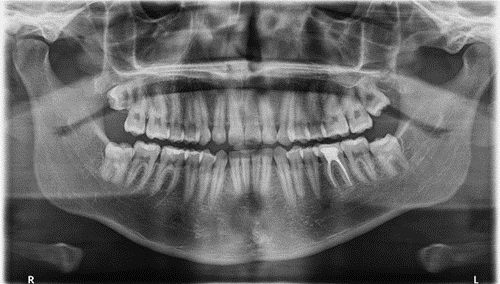

Upon radiographic examination, tooth #21 showed extensive root canal calcification with intact lamina and normal periodontal ligament space (Figure 2).

a)

b)

Figure 2. Preoperative radiographs. a)  orthopantomogram (OPG) panoramic radiograph. b) coronal and sagittal view of CBCT